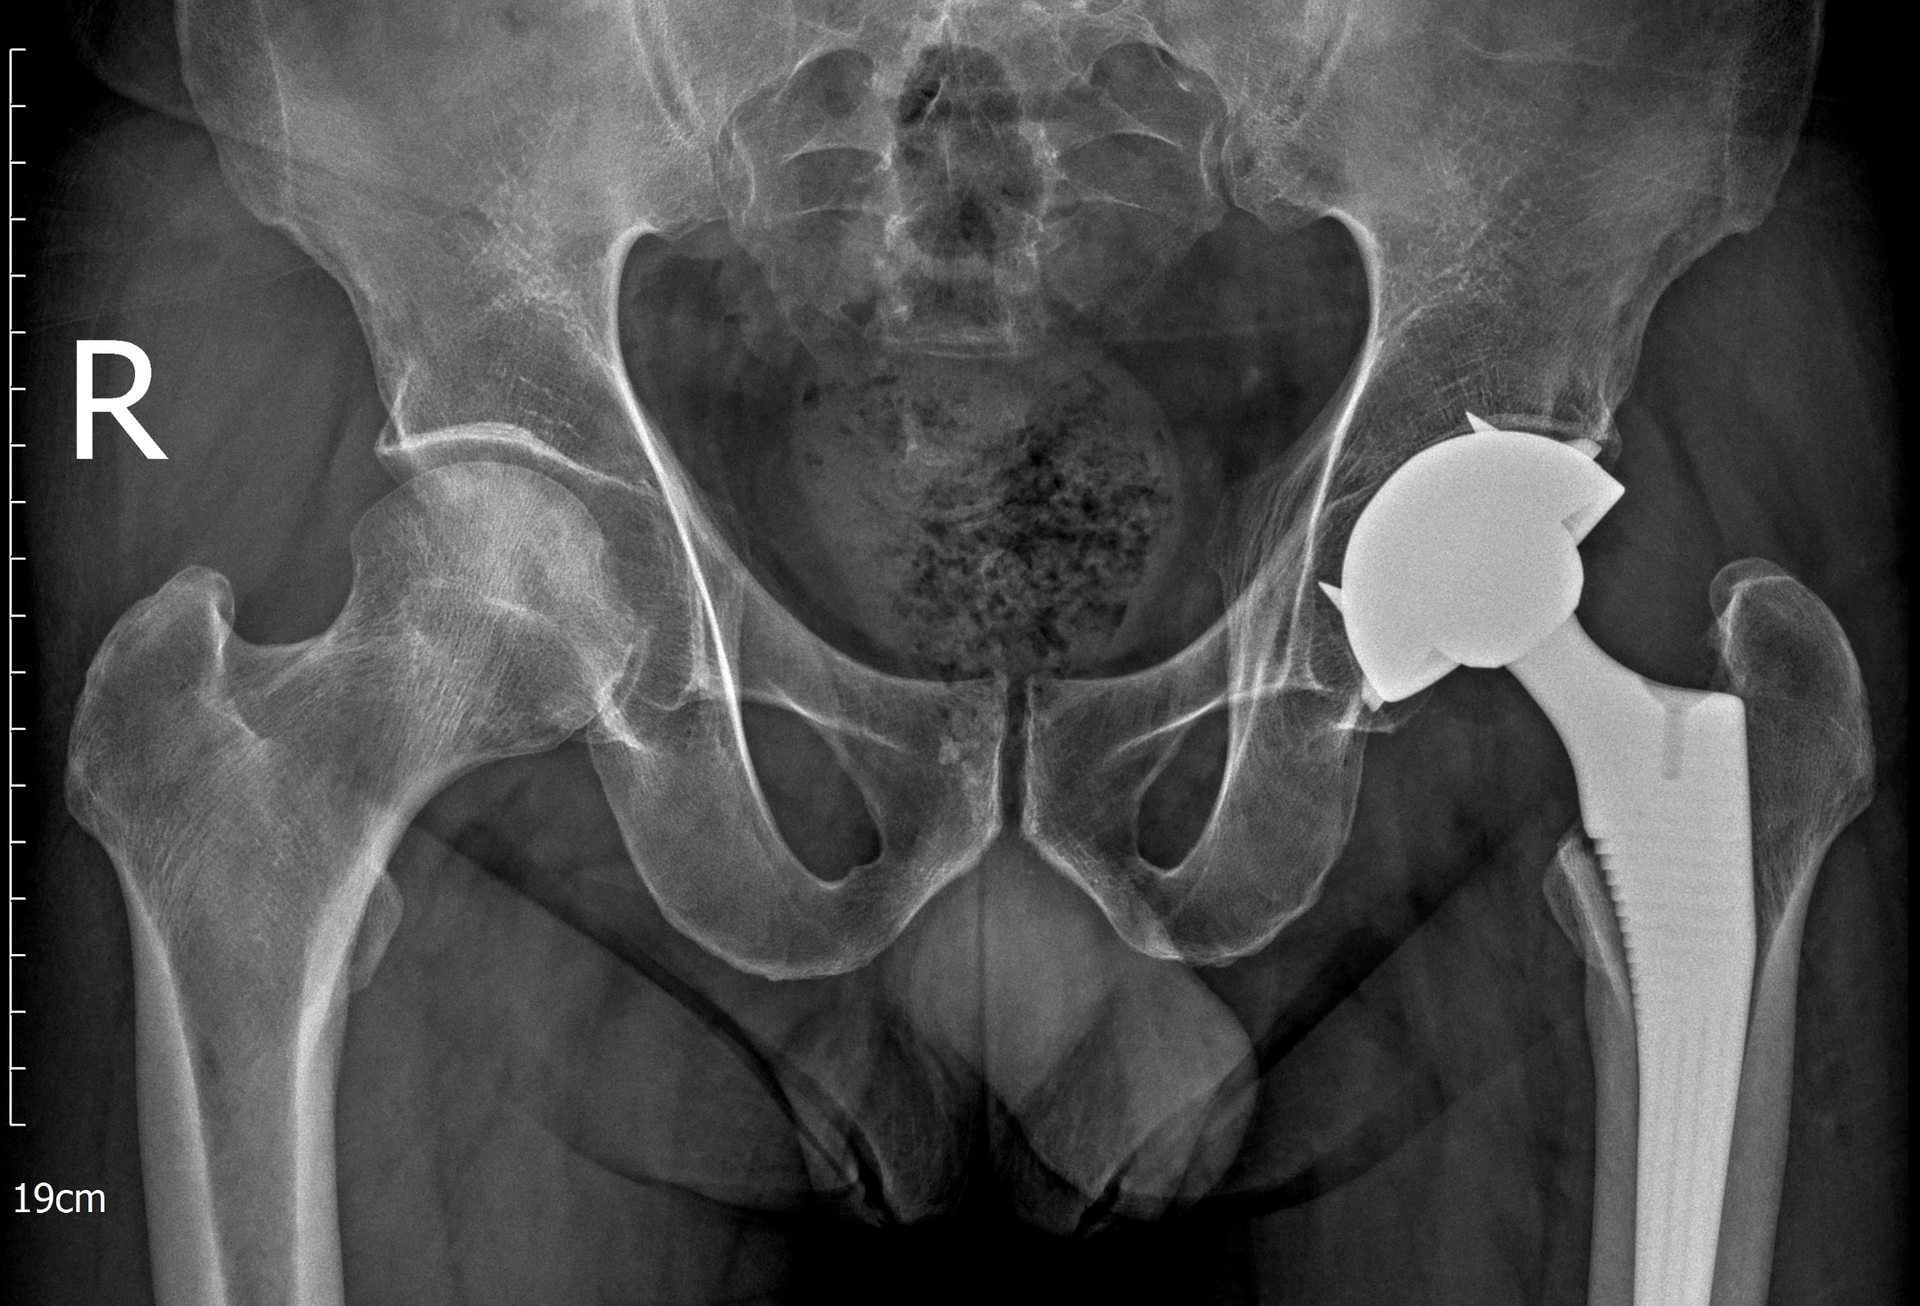

Sau khi thăm khám và đánh giá hình ảnh cận lâm sàng như X-quang, MRI, BS.CKII. Hồ Trương Đăng Triều, khoa Chấn thương chỉnh hình, Bệnh viện Hoàn Mỹ Sài Gòn nhận định: Tình trạng khớp háng bên trái của người bệnh đã tiến triển đến giai đoạn nặng không còn khả năng giữ lại, ảnh hưởng nghiêm trọng đến cấu trúc và chức năng của khớp. Việc thay khớp háng toàn phần được chỉ định nhằm phục hồi lại hình dạng của khớp, giảm đau hiệu quả và giúp người bệnh sớm quay trở lại lao động sinh hoạt như bình thường.

Trong khi đó, khớp háng phải vẫn còn khả năng bảo tồn (không thay khớp), phù hợp với phương pháp phẫu thuật giảm áp cổ xương đùi. Mục đích của phương pháp này là làm giảm áp lực bên trong xương, cải thiện tuần hoàn vùng chỏm và làm chậm quá trình hư khớp.

Ca phẫu thuật thay toàn phần khớp háng trái được thực hiện thành công bằng kĩ thuật cao và loại khớp mới nhất. Ngay sáng ngày đầu tiên sau khi mổ, anh P. đã có thể tự nâng cao chân một cách nhẹ nhàng, co duỗi háng tốt, ngồi dậy và thực hiện được các bài tập phục hồi chức năng theo chỉ dẫn.